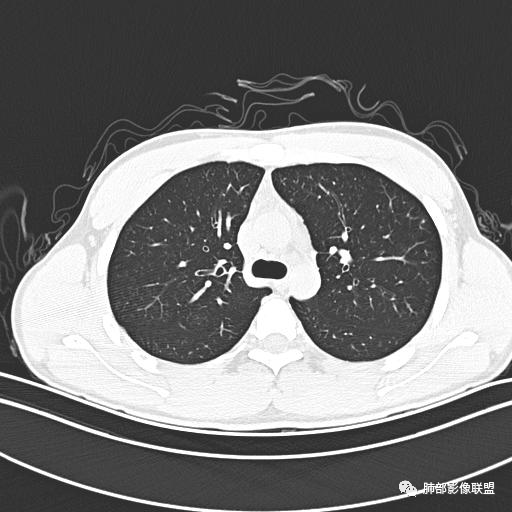

男,19岁

主  诉:发热、全身皮疹2天。

现病史:患者源于2天前受凉后出现发热,最高体温为38.5℃,且颜面部出现少量皮疹,无鼻塞、流涕、咳嗽、咳痰,未在意而未作特殊处理,次日全身皮疹逐渐增多至全身,伴轻度瘙痒,在当地卫生所给予抗病毒、抗感染治疗(具体用药不详)体温有所下降,但皮疹无明显消退,无腹痛、头痛,食欲无明显减退,为进一步诊治,遂于今日急来我院求治,患者目前精神尚可,体力正常,食欲正常,睡眠正常,体重无明显变化,大便正常,排尿正常。

小强:青年,发热,皮疹;双肺散在结节,周围磨玻璃,点晕征,疱疹病毒感染,鉴别荚膜组织胞浆菌,结核。 大雄:青年,急性起病,发热伴全身皮疹2天,抗病毒治疗体温有下降。双肺随机分布大小不等类圆结节,“点晕征”。考虑水痘-疱疹病毒(VZV)血播询问接触史,查体皮疹分布以及形态基本可诊断。 王开金江津中心医院呼吸科:青年男性,起病急,病程短,以发热,皮疹为首发症状,感染指标以单核细胞升高为主,胸部ct双肺多发结界,周围有晕,点晕表现,随机分布,同意於老师意见,水痘疱疹病毒血流感染累及肺。 王秀仙:双肺多发大小不等结节,周围有晕,边缘模糊,呈点晕征表现。青年,急性起病,发热伴全身皮疹2天,抗病毒治疗体温有下降。考虑疱疹病毒。鉴别荚膜组织胞浆菌。 傅昌瑜:19岁男性,发热、全身皮疹2天,单核细胞增高,双肺多发结节,结节边缘见边界不清磨玻璃影。点晕征+发热、全身皮疹+单核细胞增高——考虑水痘-带状疱疹病毒肺炎。 一切∮随缘:年轻男性,发热,皮疹两天,实验室,CRP,PCT增高,影像:双肺多发散在磨玻璃结节,边界欠清,大小不等,呈点晕征改变,以血管束周围分布为主,局部血管束略增粗,其它无明显改变,考虑:1:病毒性肺炎(水痘疱疹病毒?不知道皮肤有无改变)2:真菌(组织胞浆菌,血管侵袭性肺曲霉)3:GPA4:寄生虫(实验室没有看到嗜酸细胞增高) 赵山河:双肺散在结节,周围有晕,边缘模糊,呈点晕征表现。青年,急性起病,发热伴全身皮疹2天,抗病毒治疗体温有下降。考虑水痘—疱疹病毒感染。洪桥爱:青年男性,发热、皮疹2天,伴瘙痒,皮疹于面部首发,之后进展至全身,虽然没有对皮疹进行描述,但是从出疹时间及皮疹进展情况,伴瘙痒,应该就是个水痘患者;CT提示双肺随机分布结节影,部分结节伴有边界不清晕征,考虑水痘血播肺。 刘强:年轻男性,急性起病,皮疹,发热,抗感染治疗体温下降,说明有效。影像表现为散在点晕征,感染类疾病谱(疱疹病毒,真菌,结核),结合年龄,皮肤皮疹,考虑水痘-疱疹病毒性肺炎。 小兜:男性,19岁,发热皮疹两天,颜面部至全身,CRP,降钙素及单核增高。CT示双肺散在小结节,周围伴磨玻璃影,点晕征,考虑为水痘-带状疱疹病毒(varicella-zoster virus,VZV)肺炎 必有路:青年,皮疹+发热+“点晕征”→水痘-疱疹病毒(VZV) 许慧良:青年男性患者,发热、皮疹2天,体温最高38.5℃,第3天皮疹扩展至全身,伴瘙痒,胸部CT:双肺多发随机分布的小结节,结节周边见边界模糊的晕征,考虑水痘病毒感染流心明智:男,19,急性起病,发热伴全身皮疹2天。出疹顺序头→全身,抗病毒有效。胸部CT:两肺多发大小不等类圆形实性小结节影,随机分布,结节周围环绕GGO,边界模糊,呈点晕征。出疹特点是关键,未提示。考虑:血播病毒性肺炎,水痘-疱疹病毒?麻疹?鉴别荚膜组织胞浆菌、TB、血管炎、寄生虫等。 浪迹天涯:病灶多为5-10mm大小结节,结节周围可见磨玻璃样的晕环,常多发,可分布于肺内任何区域,考虑水痘—带状疱疹病肺炎如果短时间内有新的一个区域浸润,更加能说明,